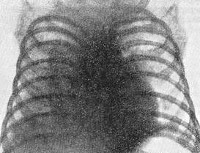

P37.0 Врожденный туберкулез